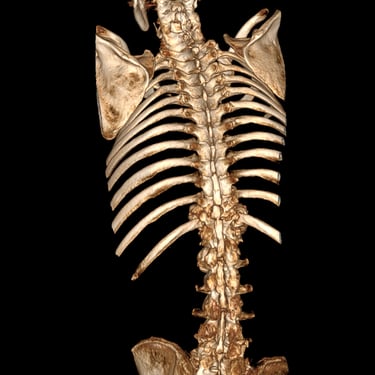

🧠Listesis Lumbar L5–S1 por Fractura Ístmica: Estabilización con FTP y TLIF.

La listesis L5–S1 por fractura ístmica causa inestabilidad y dolor. El tratamiento quirúrgico con FTP y TLIF permite descompresión neural y estabilización vertebral, mejorando la función y calidad de vida.